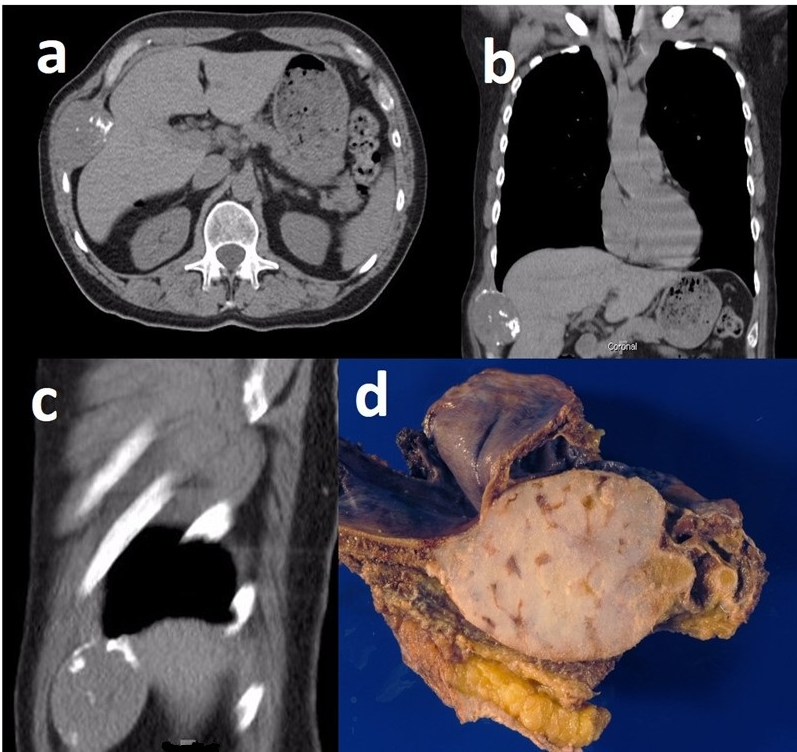

| Tumor location | Costochondral junction | 9/11 (82%) | 10/15 (67%) | 0.804 | 19/26 (73%) |

| Sternum | 2/11 (18%) | 4/15 (27%) | 6/26 (23%) | ||

| Tumor size | Mean in mm (range) | 56 (31–151) | 57 (20–127) | 0.435 | 57 (20–151) |

| Median in mm (range) | 40 (31–151) | 46 (20–127) | 45 (20–151) | ||

| Character | Lytic only | 0/11 (0%) | 3/15 (20%) | 0.238 | 3/26 (12%) |

| mixed | 11/11 (100%) | 12/15 (80%) | 23/26 (88%) | ||

| Chondroid Matrix | 0–25% | 5/11 (45%) | 10/15 (67%) | 0.551 | 15/26 (58%) |

| 25–50% | 4/11(36%) | 3/15 (20%) | 7/26 (27%) | ||

| Tumor location within the bone | Central | 5/11 (45%) | 7/15 (47%) | 1.000 | 12/26 (48%) |

| peripheral | 6/11 (55%) | 8/15 (53%) | 14/26 (52%) | ||

| Soft tissue mass | No | 3/11(27%) | 1/15 (7%) | 0.279 | 4/26 (15%) |

| Yes | 8/11(73%) | 14/15 (93%) | 22/26 (85%) |